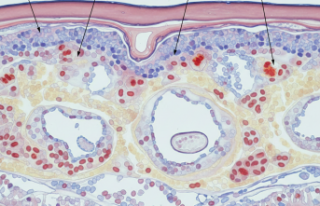

Hastalık kondroektodermal displazi (kemik ve deri gelişim bozukluğu) olarak da biliniyor. Uzmanlar iskelet sistemindeki bu değişimlerin anne karnında başladığını belirtiyor. Tanı süreci genellikle radyolojik görüntüleme ve klinik muayene ile tamamlanıyor.

Bu durum genellikle dar bir göğüs kafesi ve kısalmış kollarla kendini belli ediyor. Tabii bir de polidaktili (fazla parmaklılık) meselesi var ki, en belirgin işaretlerden biri sayılır. Aileler genelde doğum anında fark ediyor bu durumu. Hafif bir şaşkınlık, sonra o malum endişe başlıyor. Acaba kalbinde bir sorun var mı? Maalesef bu çocukların yarısına yakınında doğuştan kalp delikleri görülebiliyor.